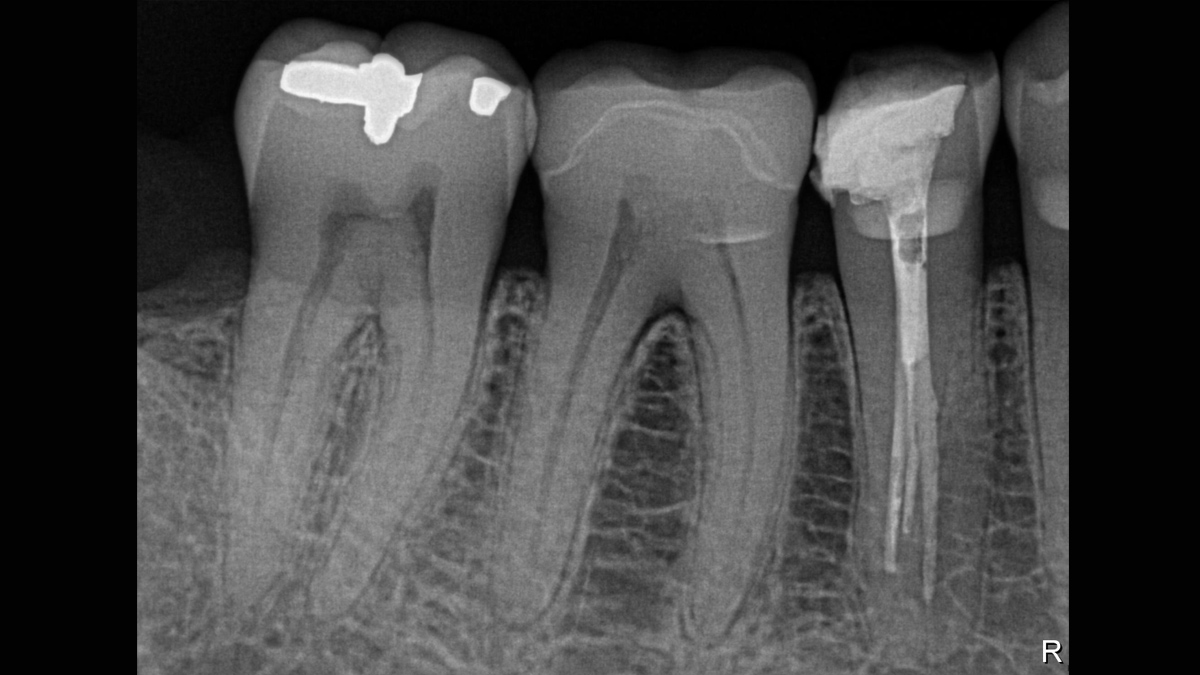

Xios XG Supreme proporciona una resolución teórica de 33 pl/mm y un tamaño de píxel de 15 μm que ofrece una excelente calidad de imagen sin el tiempo de espera adicional causado por un proceso de revelado o escaneo.

La excepcional calidad de las imágenes es solo el comienzo con los sensores intraorales Xios XG Supreme. El deslizador de nitidez dinámica le permite ajustar las configuraciones de su diagnóstico en términos de nitidez. Hay disponibles opciones adicionales del deslizador para modificaciones de brillo y contraste. Después de la configuración, las imágenes se muestran de manera eficiente para mejorar sus capacidades de diagnóstico, lo que le ahorra tiempo valioso. Un solo clic del mouse le permite obtener la imagen correcta para cada situación de tratamiento y mejor soporte clínico.

Los sensores Xios XG Supreme tienen cinco opciones diferentes de filtro: odontología general, endodoncia, periodoncia, restauración y caries. Estas vistas clínicamente específicas están diseñadas para optimizar su diagnóstico, mejorando la imagen para satisfacer sus necesidades.